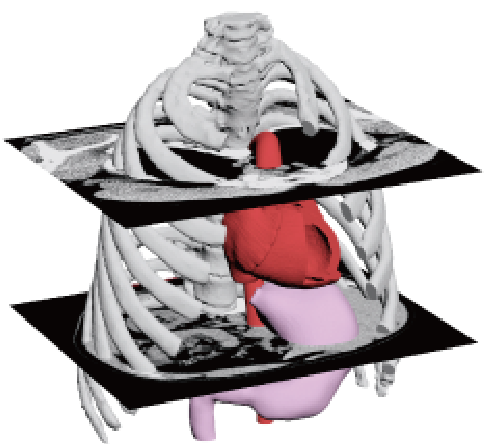

- Reads DICOM data obtained from CT imaging into mimics

We will convert the data into 3D data

and confirm with the customer that

the area of interest has been reproduced in the image or data.*If the STL output is available directly from the medical workstation,